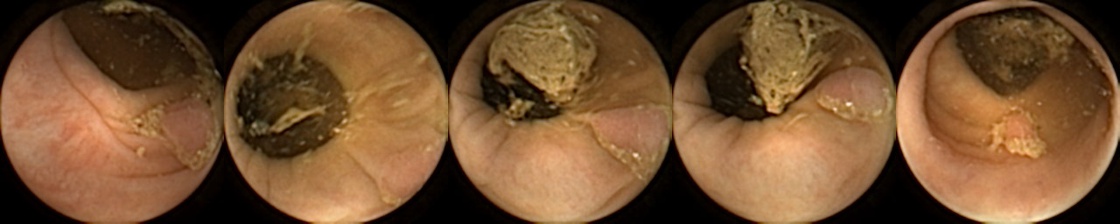

Similarly, we consider examples for the MIV model based on SimCLR pretraining using the pretrained ConvNext backbone in Figure 4. The model has a test accuracy of 86.26% for DBA L1 with 2 heads. Here we note again a similar trend by looking at the True Positive and False Negative examples as observed before, where a significant difference in the query image when compared with the target images can lead to a failure to identify the same polyp images in the five examples. A look at the False Positive examples affirms that the task remains challenging, as evidenced by the model’s occasional misclassifications in ambiguous cases.

True Positive False Negative

Refer to caption Refer to caption

False Positive True Negative

Figure 4: True Positives (Pred = true, Label = true), False Negatives (Pred = false, Label = true), False Positives (Pred = true, Label = false),True Negatives (Pred = false, Label = false) for the DBA L1(h=2) model applying SimCLR using the ConvNeXt backbone. In each row, the leftmost image is the query and the 4 images to the right of each query are the target images.